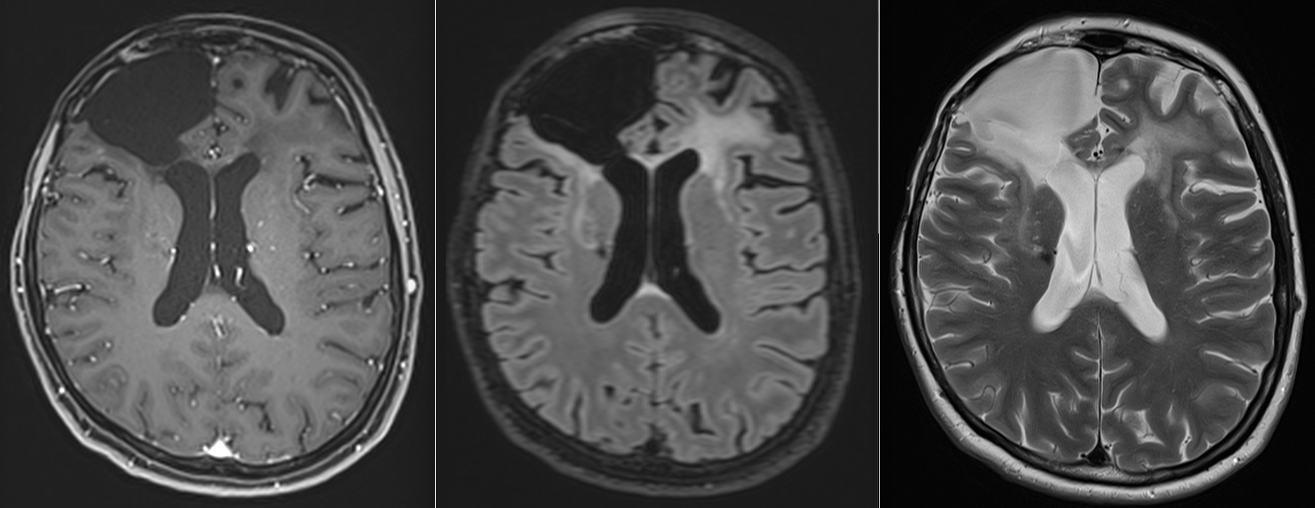

RMN-urile succesive au arătat:

- absența progresiei leziunii

- stabilitate imagistică

- lipsa transformării către un fenotip agresiv